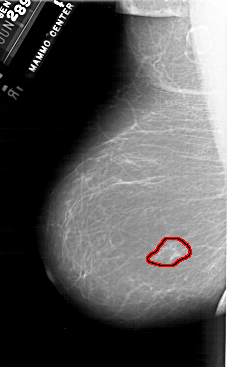

FILE: A_1902_1.LEFT_MLO.OVERLAY

TOTAL_ABNORMALITIES 1

ABNORMALITY 1

LESION_TYPE MASS SHAPE IRREGULAR MARGINS ILL_DEFINED

ASSESSMENT 4

SUBTLETY 3

PATHOLOGY MALIGNANT

TOTAL_OUTLINES 1

BOUNDARY